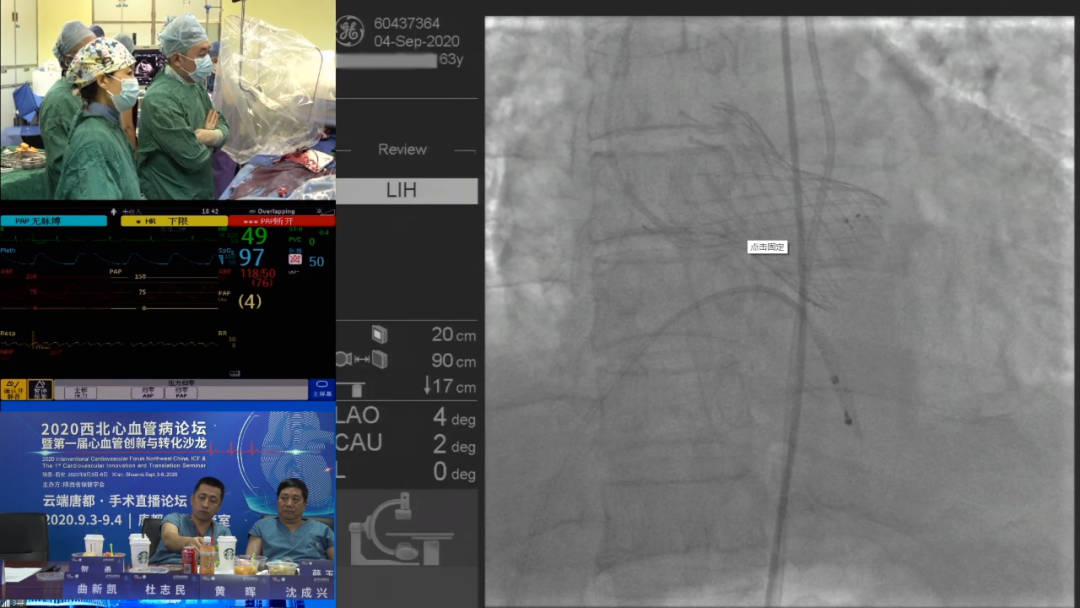

李妍教授、罗建方教授通力协作,完成一例挑战性TAVR手术